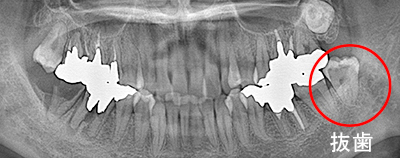

Before

After

左下の親知らずの歯を移植の症例です。